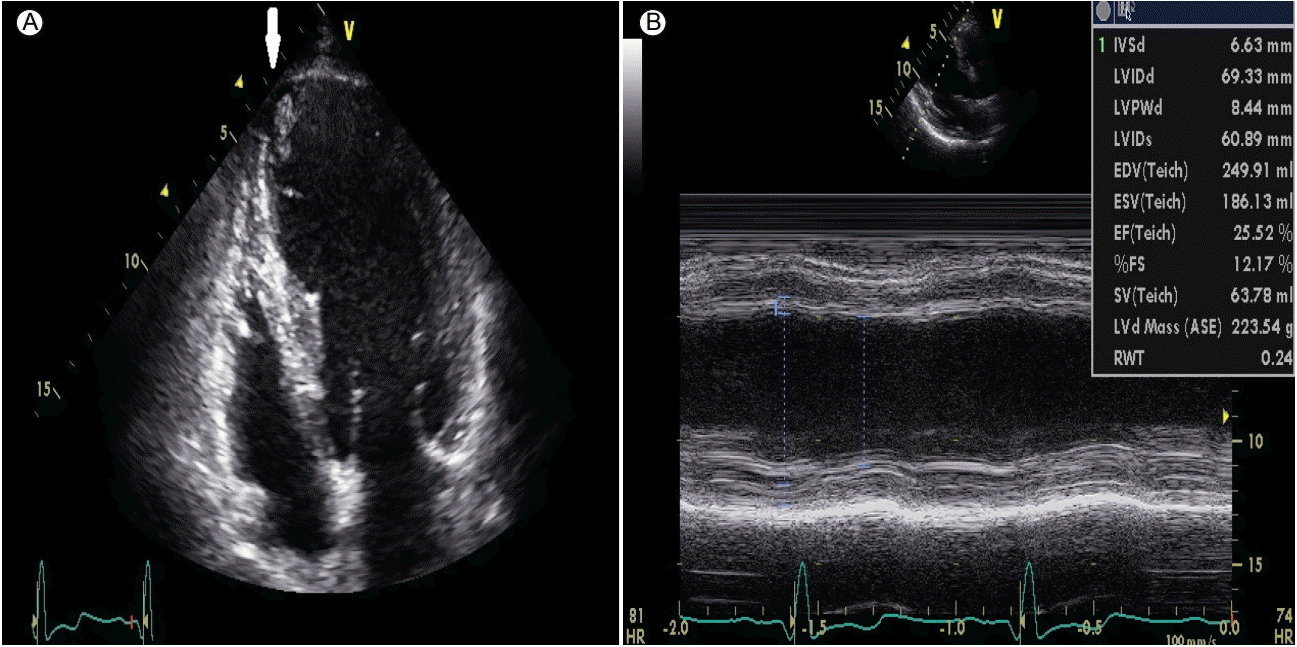

Figure 1.

Echocardiography showed (A) round-shaped mobile echogenic mass (arrow) (14 × 11 mm, 12 × 10 mm) on left ventricular (LV) apex in an apical four-chamber view, suggesting LV thrombi, and (B), a decreased ejection fraction of 22%.